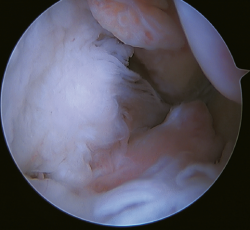

Figura 5. Rotura del ligamento talofibular anterior y del ligamento calcaneofibular con mala calidad tisular del remanente ligamentoso.